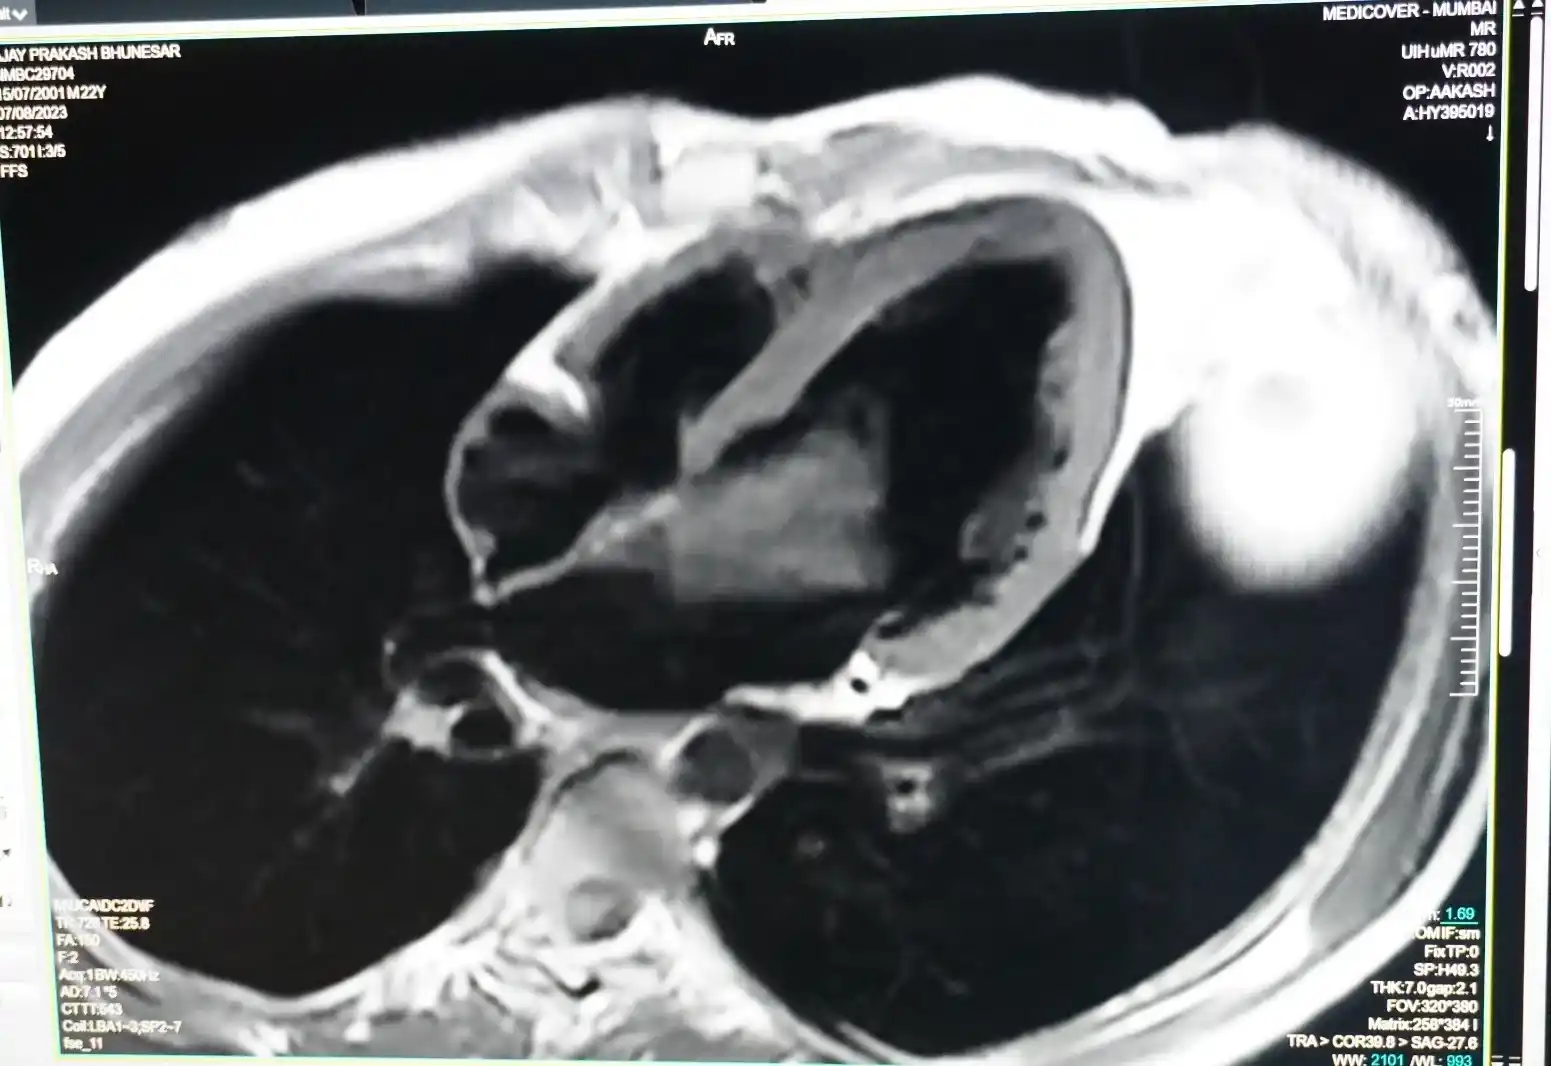

22 year male patient presented with ataxia,difficulty in swallowing,vomitings and weakness and decreased sensation in limbs. His MRI brain showed non hemorrhagic infarct involving Dorsolateral medulla.He was evaluated for cause of development of stroke.On detail evaluation by cardiologist his ECHO showed Large irregular mobile mass measuring 6.3 x3.8 cm,present in LA extending to LV so differential diagnosis of LA myxoma,Large clot or vegetation was kept.Cardiac MRI showed a large well defined heterogeneously enhancing lobulated,oval,mobile,pedunculated mass in left atrium attached to the interatrial septum with prolapse into left ventricle through AV valve likely Left atrial myxoma.

Pre Surgery MRI